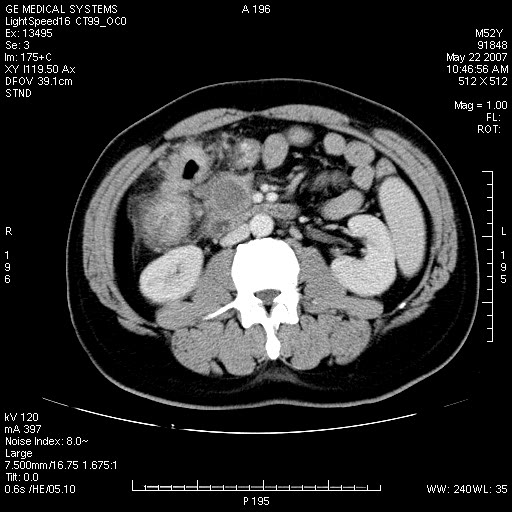

以下是引用余辉在2007-5-22 20:12:00的发言:[br]升结肠管壁明显增厚,增强有静脉期持续增强,结合患者病史,考虑结肠癌可能性大,临近脂肪影密度增高,混浊,恐有肠系膜浸润转移,建议镜检

以下是引用dyqct在2007-5-22 20:43:00的发言:[br]支持结肠肝曲占位性病变(浸润型结肠癌可能性大)。胆总管下端扩张,原因待查。

以下是引用gaoxiao在2007-5-22 20:49:00的发言:[br]考虑升结肠癌向周围侵犯,胰头钩突受侵。